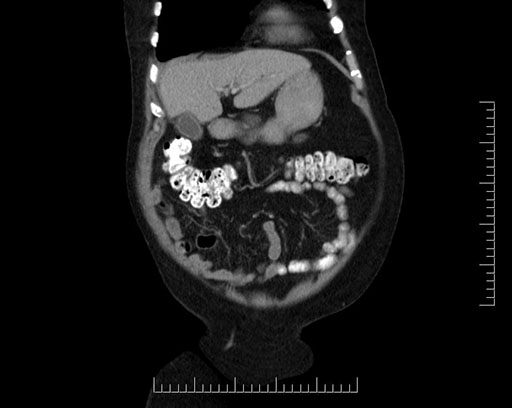

Whipple (pancreaticoduodenectomy) [case 7]

Imaging Analysis

Look through the patient's CT scan to identify any areas of concern for the necessary procedure.

Based on your CT findings, which issue(s) would give reason for "planned slowing down moment(s)" in this case?

Considering a standard Whipple procedure, what step(s) of the operation would you do differently in this case?